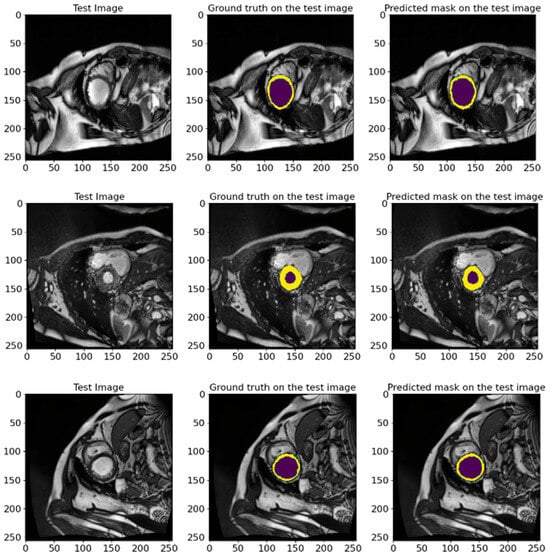

In Figure 16, we show random samples from the test set, along with their GT masks and the predicted masks generated by the model. This visualization illustrates the comparison between the manual annotation conducted with the help of experienced cardiologists and the segmentation outcomes acquired using the developed model. The actual labels represent the true state of the segmented regions and are presented in each image for visual comparison. Looking at the predictions of the model, they indicate how accurately it can reproduce the contours and shapes of the left ventricle and myocardium. The comparison of the images in Figure 16 attests to the high accuracy of the model since the predicted segmentations almost entirely match the actual labels. It further highlights the model’s applicability in clinical settings and its ability to conduct the segmentation task on cardiac MRI images efficiently.

Figure 16.

The visual presentation of random samples of images from the test set from the ACDC 2017 database, with the actual and predicted GT by the model. The visualization shows the comparison between the manual annotation conducted with experienced cardiologists and the segmentation results obtained using the developed model. The deep violet marks the LV regions, whereas yellow outlines the Myo. The high degree of agreement between predictions and actual labels authenticates the precision and reliability of our proposed model in segmenting cardiac MRI images.